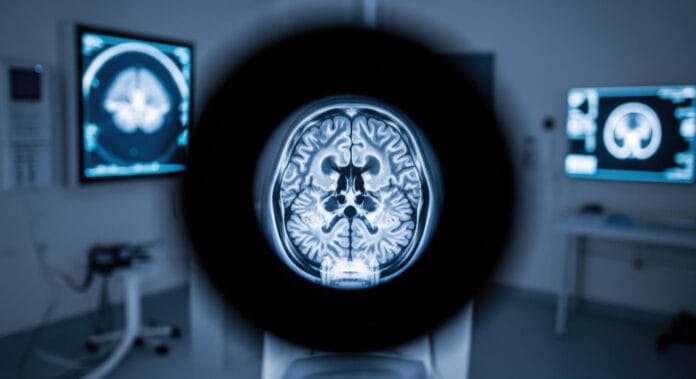

CT-ul cerebral – tomografia computerizată a creierului – reprezintă instrumentul esențial pentru medicii de urgență, oferind imagini detaliate în doar câteva minute și facilitând luarea rapidă a deciziilor critice în cazuri de traumă, sângerare sau alte afecțiuni neurologice.

Tomografia computerizată (CT) folosește raze X pentru a crea secțiuni transversale ale creierului, reconstrucție digitală ce permite vizualizarea structurilor interne, identificarea sângerărilor, fracturilor craniene, tumorilor sau altor anomalii. Comparativ cu alte metode, CT-ul oferă un echilibru excelent între rapiditate și claritate, fiind ideal în situații de urgență.

Prin imagini axiale, coronoane și sagitale, CT-ul permite identificarea:

- Sângerărilor – hiperdensitatea caracteristică a sângelui.

- Edemului cerebral – zone hipodense ce indică acumularea de lichid.

- Fracturilor craniene – liniile radiolucente în osul cranian.

- Leziunilor ischemice timpurii – zone cu densitate redusă în primele ore de la accidentul vascular cerebral.